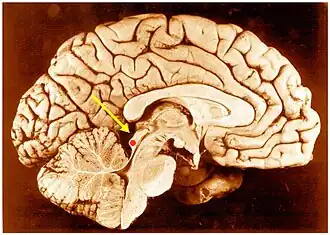

Inferior colliculus (red dot) in human brain, sagittal section. | |